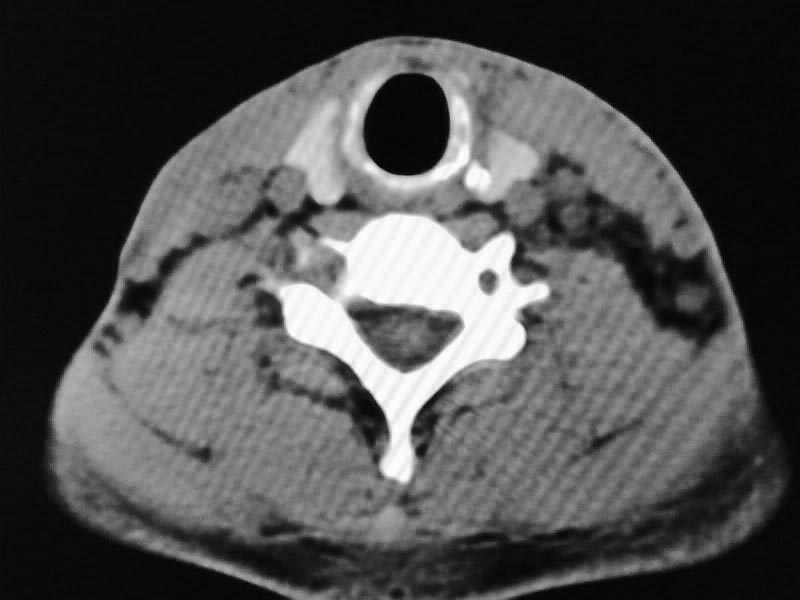

以下是引用余辉在2009-5-3 11:36:00的发言:[br]左侧胸锁乳突肌下方不规则肿物影,边界不清,内部密度不均,左侧颈外侧区脂肪增多,多发淋巴结肿大,考虑淋巴或神经来源肿瘤可能性大,不除外淋巴结炎,肌源性肿瘤及增生性肌炎等,活检